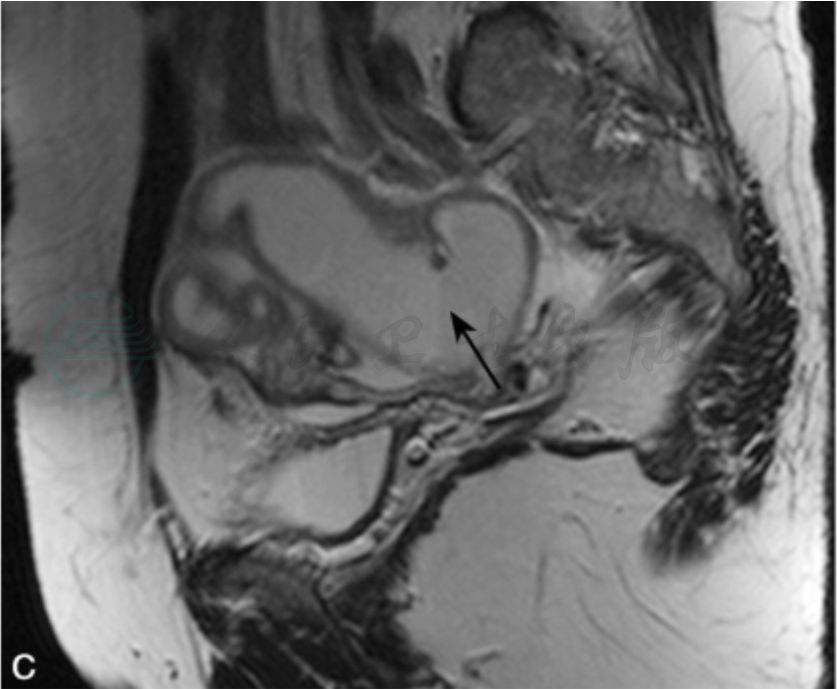

图1

女性,44岁,下腹痛一周,左侧输卵管积脓横断位T1WI脂肪抑制(A)、T2WI脂肪抑制(B)及矢状位T2WI(C)见左附件区粗细不均、扭曲折叠的管状结构(Ⅰ型),内见液-液平面(黑箭);增强(D)后可见管壁较均匀增厚(大于0.25cm)。DWI(E)(b值800)见囊液呈上低下高信号,囊液下部ADC值为1.35×10-3mm2/s。矢状位有利于观察病灶的整体形态。U:子宫。